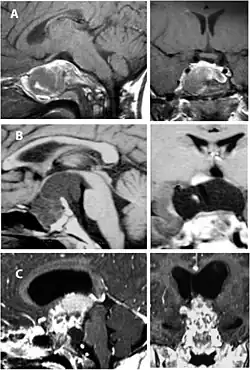

Badania obrazowe

W tomografii komputerowej guz ma postać torbielowatej, hipodensyjnej masy, często z obecnymi nawapnieniami, położonej w linii środkowej. Część lita guza może ulegać wzmocnieniu kontrastowemu.